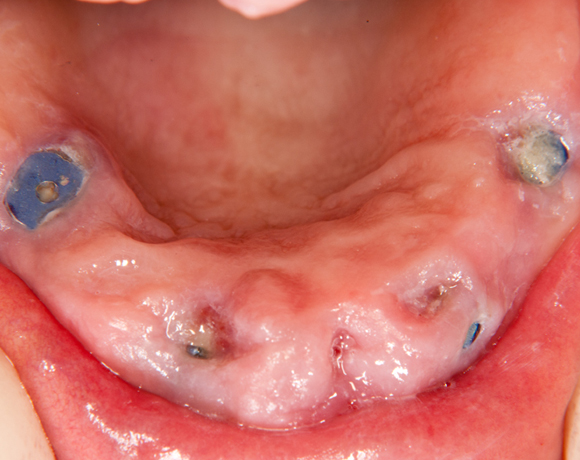

Der SFI-Bar® ist die innovative Steglösung für die abnehmbare Prothetik auf 2-6 Implantaten im Ober- und Unterkiefer.

Mit einer überschaubaren Zahl an präfabrizierten Systemkomponenten lassen sich schnell passgenaue Stegversorgungen für praktisch jede klinische Situation herstellen.

Der SFI-Bar® ist kompatibel mit einer Vielzahl von Implantatsystemen. Hier ein Beispiel mit SPI- Element Implantaten der Firma Thommen Medical AG